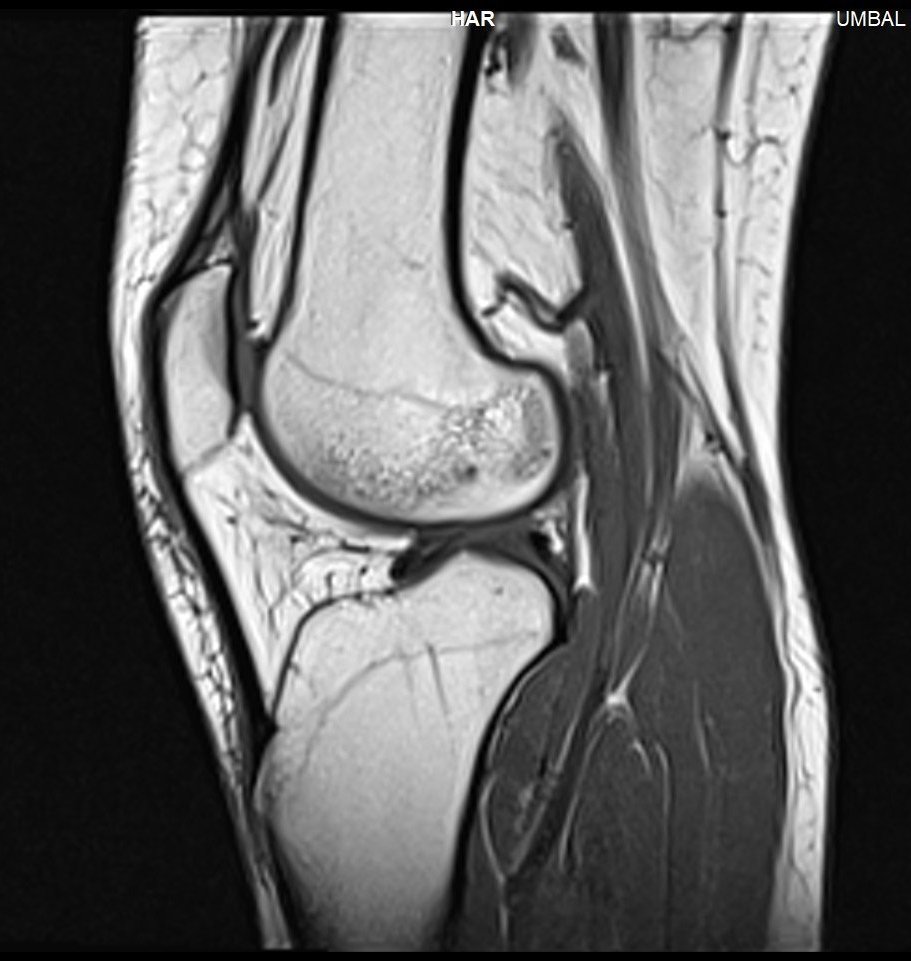

Здравейте, тъй като незнам как да ви кача целия диск Ви качвам малко снимки

Здравейте, благодаря за ЯМР-а.

Подборът на срезове/снимки не е най- добрият. Моля да изпратите диска на имейл: infо@beta-clinic.com или чрез спедитор на адреса на Бета клиник.